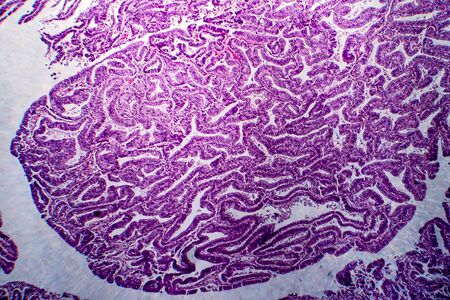

Ovarian cancer, light micrograph, photo under microscope. Photograph shows a fragment of a cancerous tumor in the female ovary. Selective focus